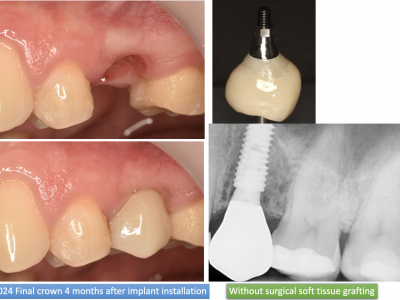

Each case is documented with clinical pictures before, after and during operation. For most of the cases there is surgical video. CBCT before, in the OP day and 4 months after, or longer period of time will demonstrate the volume of buccal bone and soft tissue. Depends of time available, between 13 and 20 clinical cases can be shown.